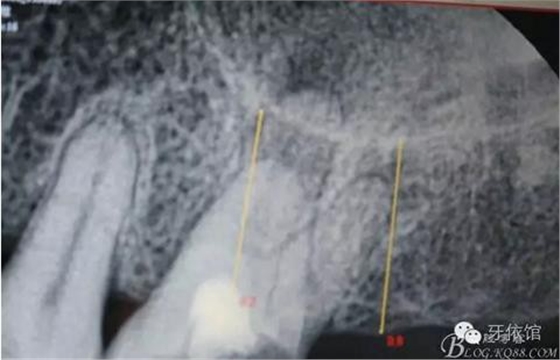

X光片

患者女,45歲,右上6于多年前牙髓失活后充填,未作冠,術前不久,進食時不幸劈裂。檢查發(fā)現(xiàn):右上6充填物脫落,近遠中向縱劈,x光見根管內(nèi)無充填物。同時有右上7、右下7缺失。計劃:右上6,7,右下7種植修復。右上6為即可種植,同時做內(nèi)提。